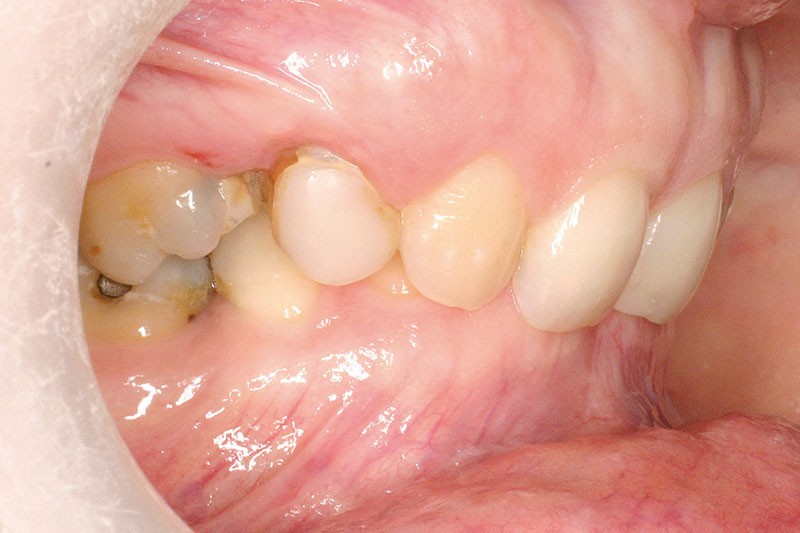

La patiente, âgée de 30 ans, présente des agénésies multiples : 12, 22, 14, 15, 24, 25, 35 et 45 (fig. 1 à 3).

Un traitement orthodontique a déjà été effectué pendant son adolescence avec un choix de fermeture d’espaces qui a entraîné une linguoversion incisive maxillaire excessive (fig. 10), avec un préjudice esthétique important notamment sur le sourire (fig. 11 à 13).